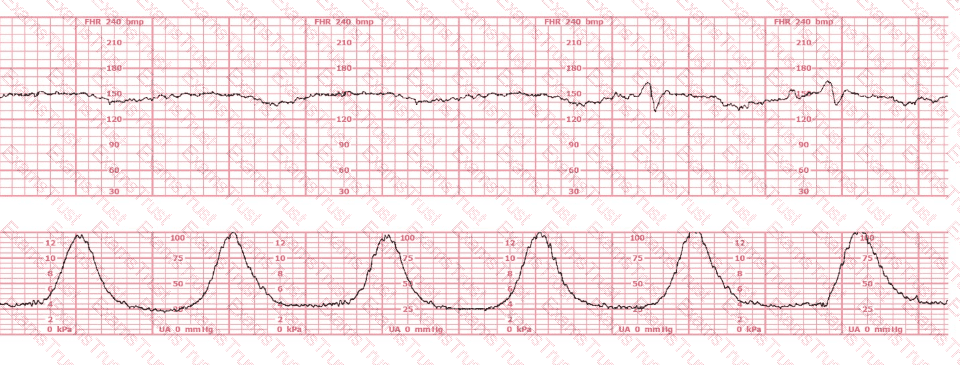

A patient at 41 weeks gestation is being induced. She has progressed slowly and is now at 6 cm, 90% effaced, –1 station. She has the fetal heart tracing shown despite repositioning. The next step in the management of this patient should be to: